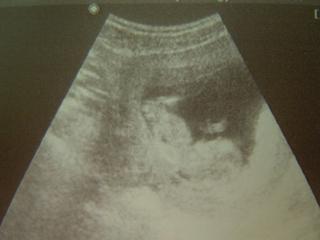

Ahoj holky, kontrola dopadla výborně 🙂 Tlak ukázkový 120/80. Předpokládaný termín porodu podle ET je 15.12., podle utz 13.12. Nevím, proč mi to tady píše 13tt, když jsem teprve 12tt (přesně 11tt+5. Další kontrola až 21.6. Mám i fotečku, dodám ji až po obědě, jak prcek usne. Jinak mě čeká EKG, zubař a ten screening. Musím se hnedka obědnat. Ptala jsem se zda je povinný. Tak u Dominička před těmi třemi lety se to nevyžadovalo, ale teď to doporučují. Tak zase budeme o 1000,- chudší ☹

@ronecek ahojek a me fotecku neposilas jo?? 😢 Stejne sem si ji prohlidla,hec, 😝, je krasny ten tvuj drobecek 😵 😵 😵 posilam mu pusinky 😵 😵 😵